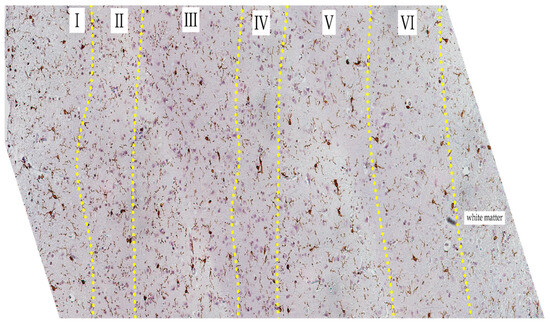

Figure 7.

Cortical region of the SAH group slide. Iba-1 staining, hematoxylin contrast. Magnification 20x. Yellow dot-line indicates the border between layers. Layers indicated in Roman numerals.